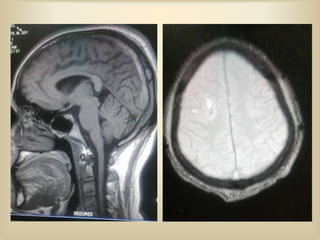

 35 year old male patient, a chronic alcoholic

presented to casualty with history of

headache 1 week, sudden onset,

gradual progression,

associated with blurring of vision.

An episode of vomiting X 1 day.

 O/E Patient was conscious oriented, looked

distressed and had R lateral rectus palsy (diplopia)

on CNS examination.

 Urgent imaging (CT-Brain) was done,

FOLLOWING THE ABNORMAL CT

FINDINGS, MRI BRAIN WAS TAKEN